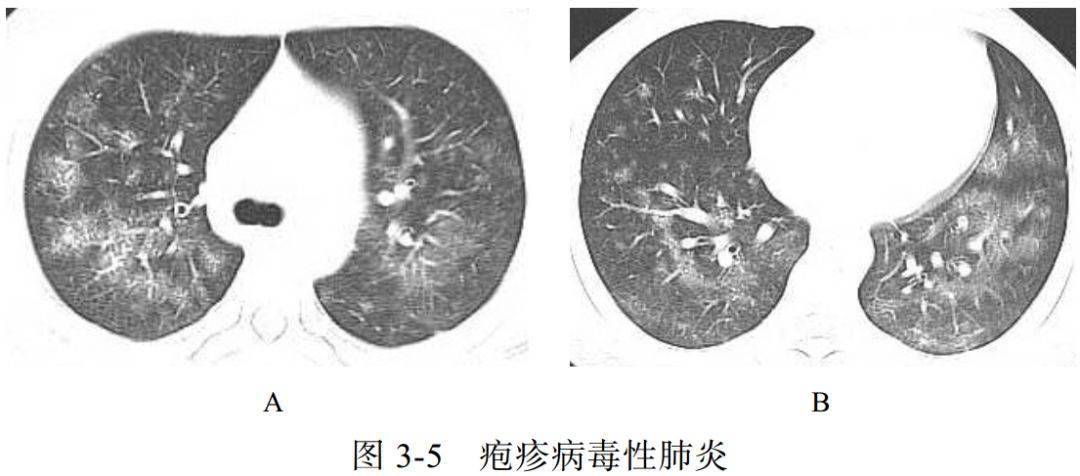

(五)疱疹病毒性肺炎

人类疱疹病毒(HSV)是一大类的 DNA 病毒,严重致病性人类疱疹病毒包括 HSV-1、 HSV-2

疱疹病毒性肺炎主要是由 HSV-1 引起的,在免疫功能低下的患者或气管插管时气道受到创伤的患者,以及烟雾吸入或慢性吸烟患者中相对常见

影像学表现

(1)包括斑片状肺叶、肺段或亚段性的实变影和磨玻璃样影(图 3-5A),间质分布小网格影(图 3-5B)

(2)可合并小叶中央结节及树芽征

(3)结节周围也可环绕磨玻璃样“晕环”

(4)多有胸腔积液出现